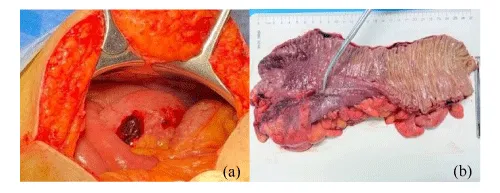

Laparotomy was done under general anaesthesia. There was free air and a small area of perforation (0.8 mm) in ascending colon. On cut section, mucosal congestion with submucosal haemorrhagic areas were seen. There was no growth or ulcer. There was no pseudo-membrane (Figure 3).